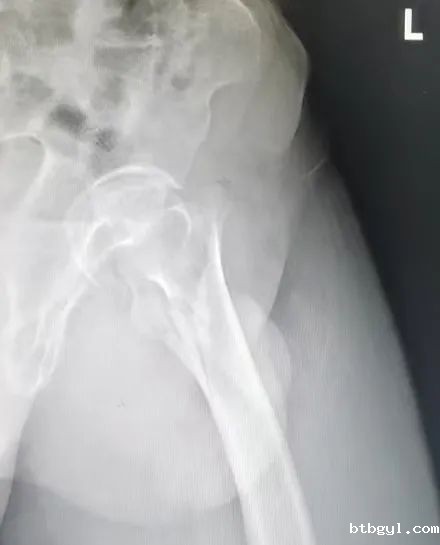

前段时间,百岁高龄的赵奶奶在家下楼时不慎踩滑摔倒受伤,因“左侧股骨转子间骨折”收入骨科(创伤中心)住院治疗。入院后赵奶奶及家人非常希望通过治疗后能站起来,下床自由行走。由于患者超高龄,基础性疾病多(合并高血压、肺部感染、双侧胸腔积液、肺气肿、硬膜下积液、贫血等多种疾病),心脑肺储备功能差,手术及麻醉风险极大。骨科(创伤中心)负责人韩雪峰、管床医生周成彬联合麻醉科手术室医护团队多次对老人的病情进行充分的术前评估,制定周密麻醉手术方案,拟采用技术成熟的椎管内麻醉下行股骨转子间骨折闭合复位髓腔钉内固定术。入院第三天,两个团队精细配合,顺利完成手术。整个手术过程老人呼吸平稳、循环稳定,尤其是麻醉科主治医师范瀚文全程陪伴赵奶奶,对术中容量管控、疼痛管理进行精细化处置。术后第二天,赵奶奶已能在助行器辅助下地行走。